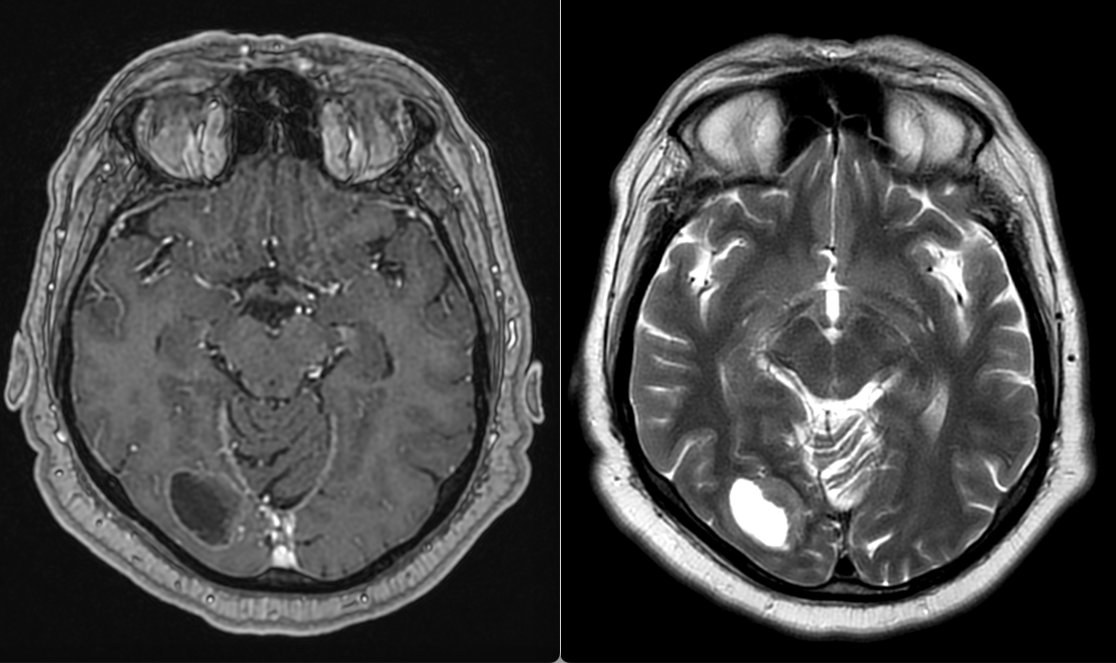

- Imagistică cerebrală: RMN-ul cu substanță de contrast este metoda de elecție, dar și CT-ul poate fi util.

Metastazele cerebrale apar frecvent în emisferele cerebrale (80%), mai rar la nivelul cerebelului (15%) sau trunchiului cerebral (5%). Localizarea influențează simptomele și posibilitățile de tratament.

Celulele canceroase se desprind din tumora primară, pătrund în vasele de sânge și călătoresc spre creier. Acolo, ele trec de bariera hemato-encefalică – o structură protectoare care apără creierul de substanțe toxice – și încep să se multiplice. De cele mai multe ori, metastazele apar în zona joncțiunii dintre substanța albă și cea cenușie, unde fluxul sanguin este bogat și viteza de circulație este mai redusă.